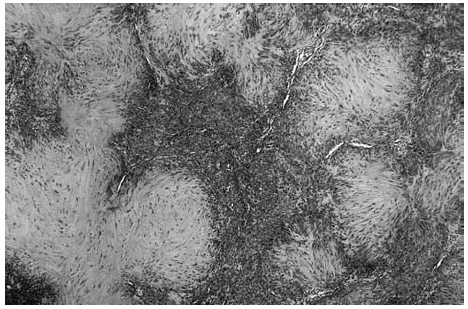

Se realizó una extirpación quirúrgica de la lesión. El estudio histopatológico mostró una tumoración dérmica multilobulillar con una zona central hipocelular, esclerosa y otra hipercelular en la periferia en la que se veían multiples espacios vasculares (fig. 2). Estas áreas más periféricas de espacios vasculares ramificados recordaban a un hemangipericitoma, y se continuaban insensiblemente con nódulos esclerosos. También se observaban nódulos hemangiopericitoides a distancia y sin conexión aparente con la tumoración principal (fig. 3).

Fig. 2.--Panorámica del tumor situado en dermis, con áreas esclerosas hipocelulares junto a otras hipercelulares. Destaca la presencia de hendiduras vasculares en la periferia de algunos nódulos.